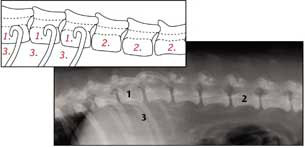

Die gesunde Wirbelsäule

1. Thoracic Rückenwirbel

2. Lumbar Rückenwirbel

3. Rippen

Rückenwirbel mit Spondylose

4. Krankhafte Knochenbildung am Rückenwirbel die anfängt zusammenzuwachsen

Auf einer seitlichen Röntgenaufnahme der Wirbelsäule kann man erkennen, dass diese „Brücken“ die Wirbel so zu verbinden beginnen,

dass Bewegungen schmerzhaft werden können. Sobald die Spangen stabil verkalkt sind, nehmen die Schmerzen ab, was allerdings